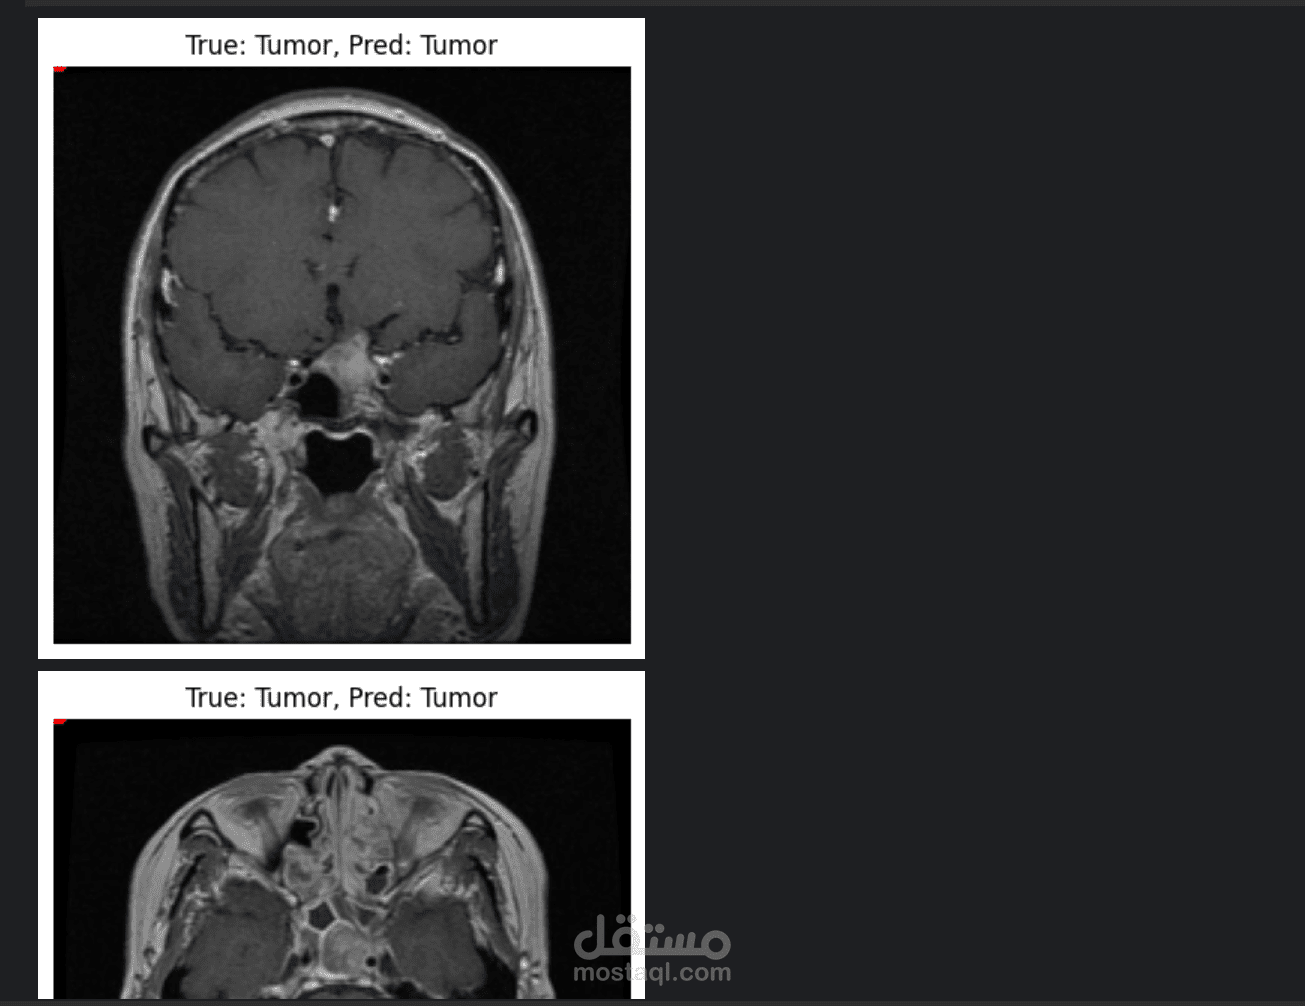

يعتبر التشخيص المبكر لأورام المخ أمراً حيوياً لإنقاذ الأرواح، ومن هنا جاء هذا المشروع لتقديم حل تقني متقدم يعتمد على الذكاء الاصطناعي (AI) وتحديداً التعلم العميق (Deep Learning). يهدف النظام إلى تحليل صور الأشعة بالرنين المغناطيسي (MRI) وتصنيفها بدقة عالية لتحديد وجود ورم من عدمه.

لقد قمت باستخدام تقنية التعلم بنقل الخبرة (Transfer Learning) من خلال توظيف نموذج ResNet50V2 العالمي، وتدريبه على مجموعة بيانات ضخمة تحتوي على صور ممسوحة ضوئياً لمرضى، مما يضمن دقة عالية وتوفيراً كبيراً في الموارد الحسابية والوقت.

توفير نموذج قادر على التنبؤ بالحالات المصابة والسليمة بدقة (Accuracy) عالية جداً، مما يجعله أداة مساعدة قوية للأطباء.